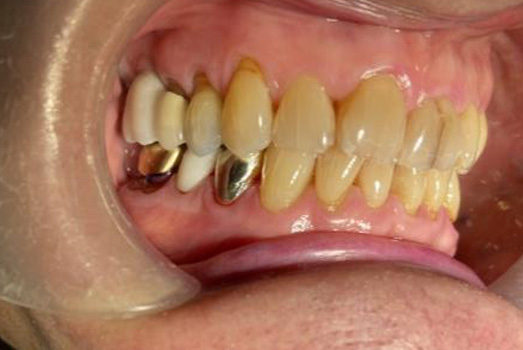

Final Intraoral Photographs